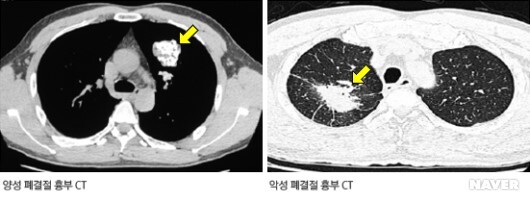

- 결절의 크기(Size of the nodule) - 의사는 보통 결절의 성장을 도표화하는데, 결절이 작을수록 양성의 가능성이 높으며 양성결절은 느리게 자라는데 비해 암성결절은 매 1~4개월마다 크기가 두배로 커짐

- 결정내용, 형태, 색깔(Nodule content, shape, and color) - 또다른 방법으로 악성과 양성을 구별하는 방법으로 칼슘함유량(calcium content)이 있음. 양성결절은 높은 칼슘함유량을 보이고 부드럽고 규칙적인 형태를 갖춤. 또한 색깔도 악성에 비해 균일한 편. 악성결절은 얼룩덜룩하고 불규칙한 형태, 거친표면, 그리고 다양한 색깔을 가짐.